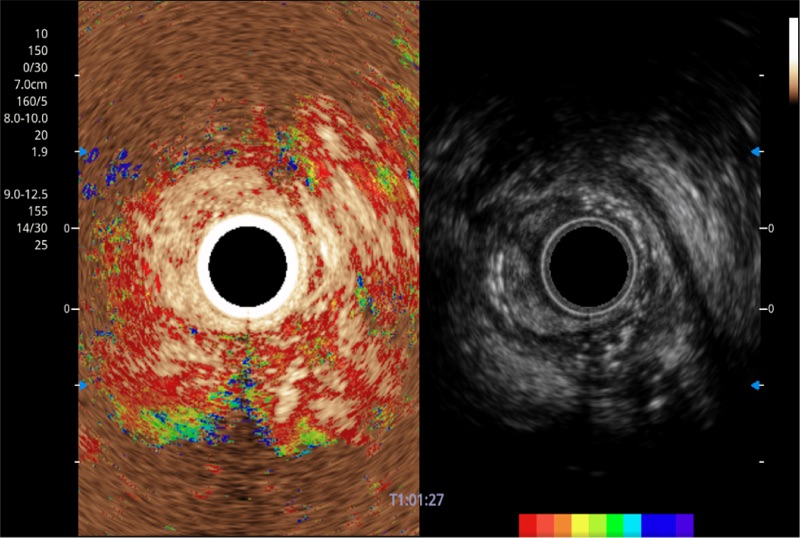

具有四种造影成像效果

食管内间质瘤清晰显像